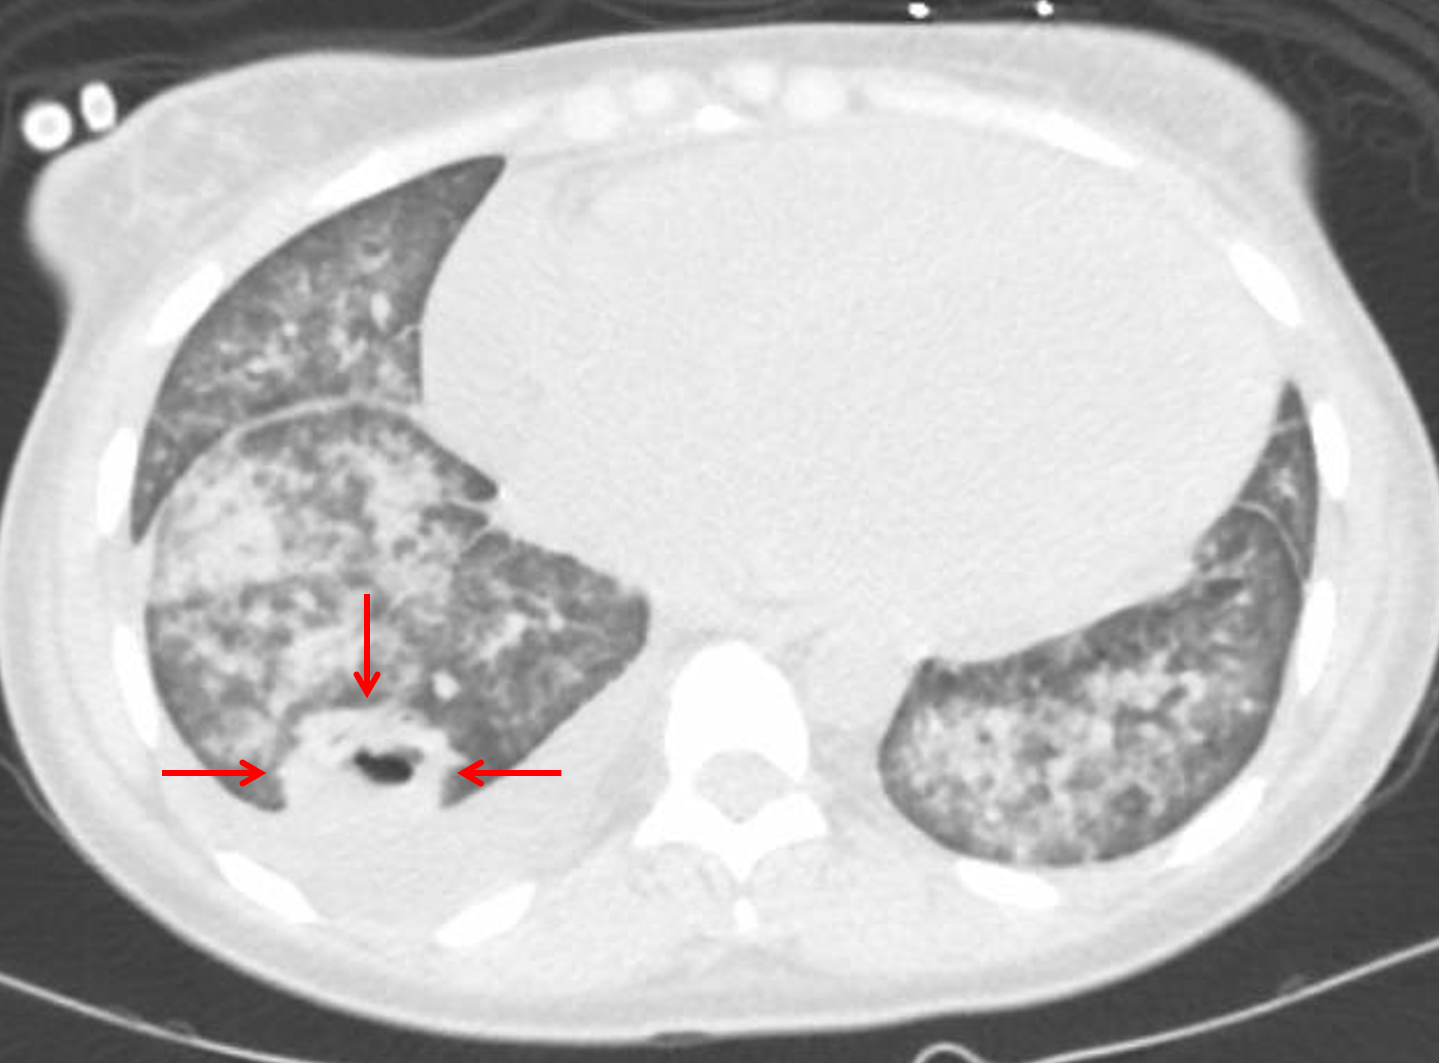

Age: 27

Sex: Female

Indication: Dyspnea, cough

Sample ReportFindings are concerning for panlobar pneumonia with a 2.5 cm right lower lobe pulmonary abscess.

Cardiomegaly with pulmonary edema and moderate-sized right and small left pleural effusions.

Moderate-sized pericardial effusion.